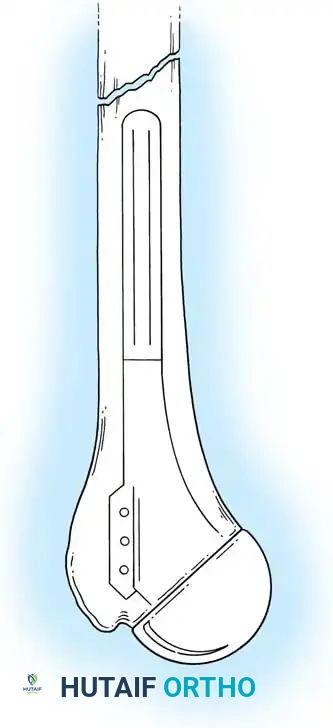

3. Humeral Head Resection

Dislocate the humeral head anteriorly through external rotation and extension. Remove peripheral osteophytes to identify the true anatomical neck. The humeral cut is made along the anatomical neck, typically at 30 degrees of retroversion and 45 degrees of inclination.

5. Humeral Preparation and Implantation

Broach the humeral canal sequentially. Assess the trial components for stability, ensuring 50% posterior translation on the "drawer test" and no superior escape. Implant the final prosthesis (press-fit or cemented based on bone quality).